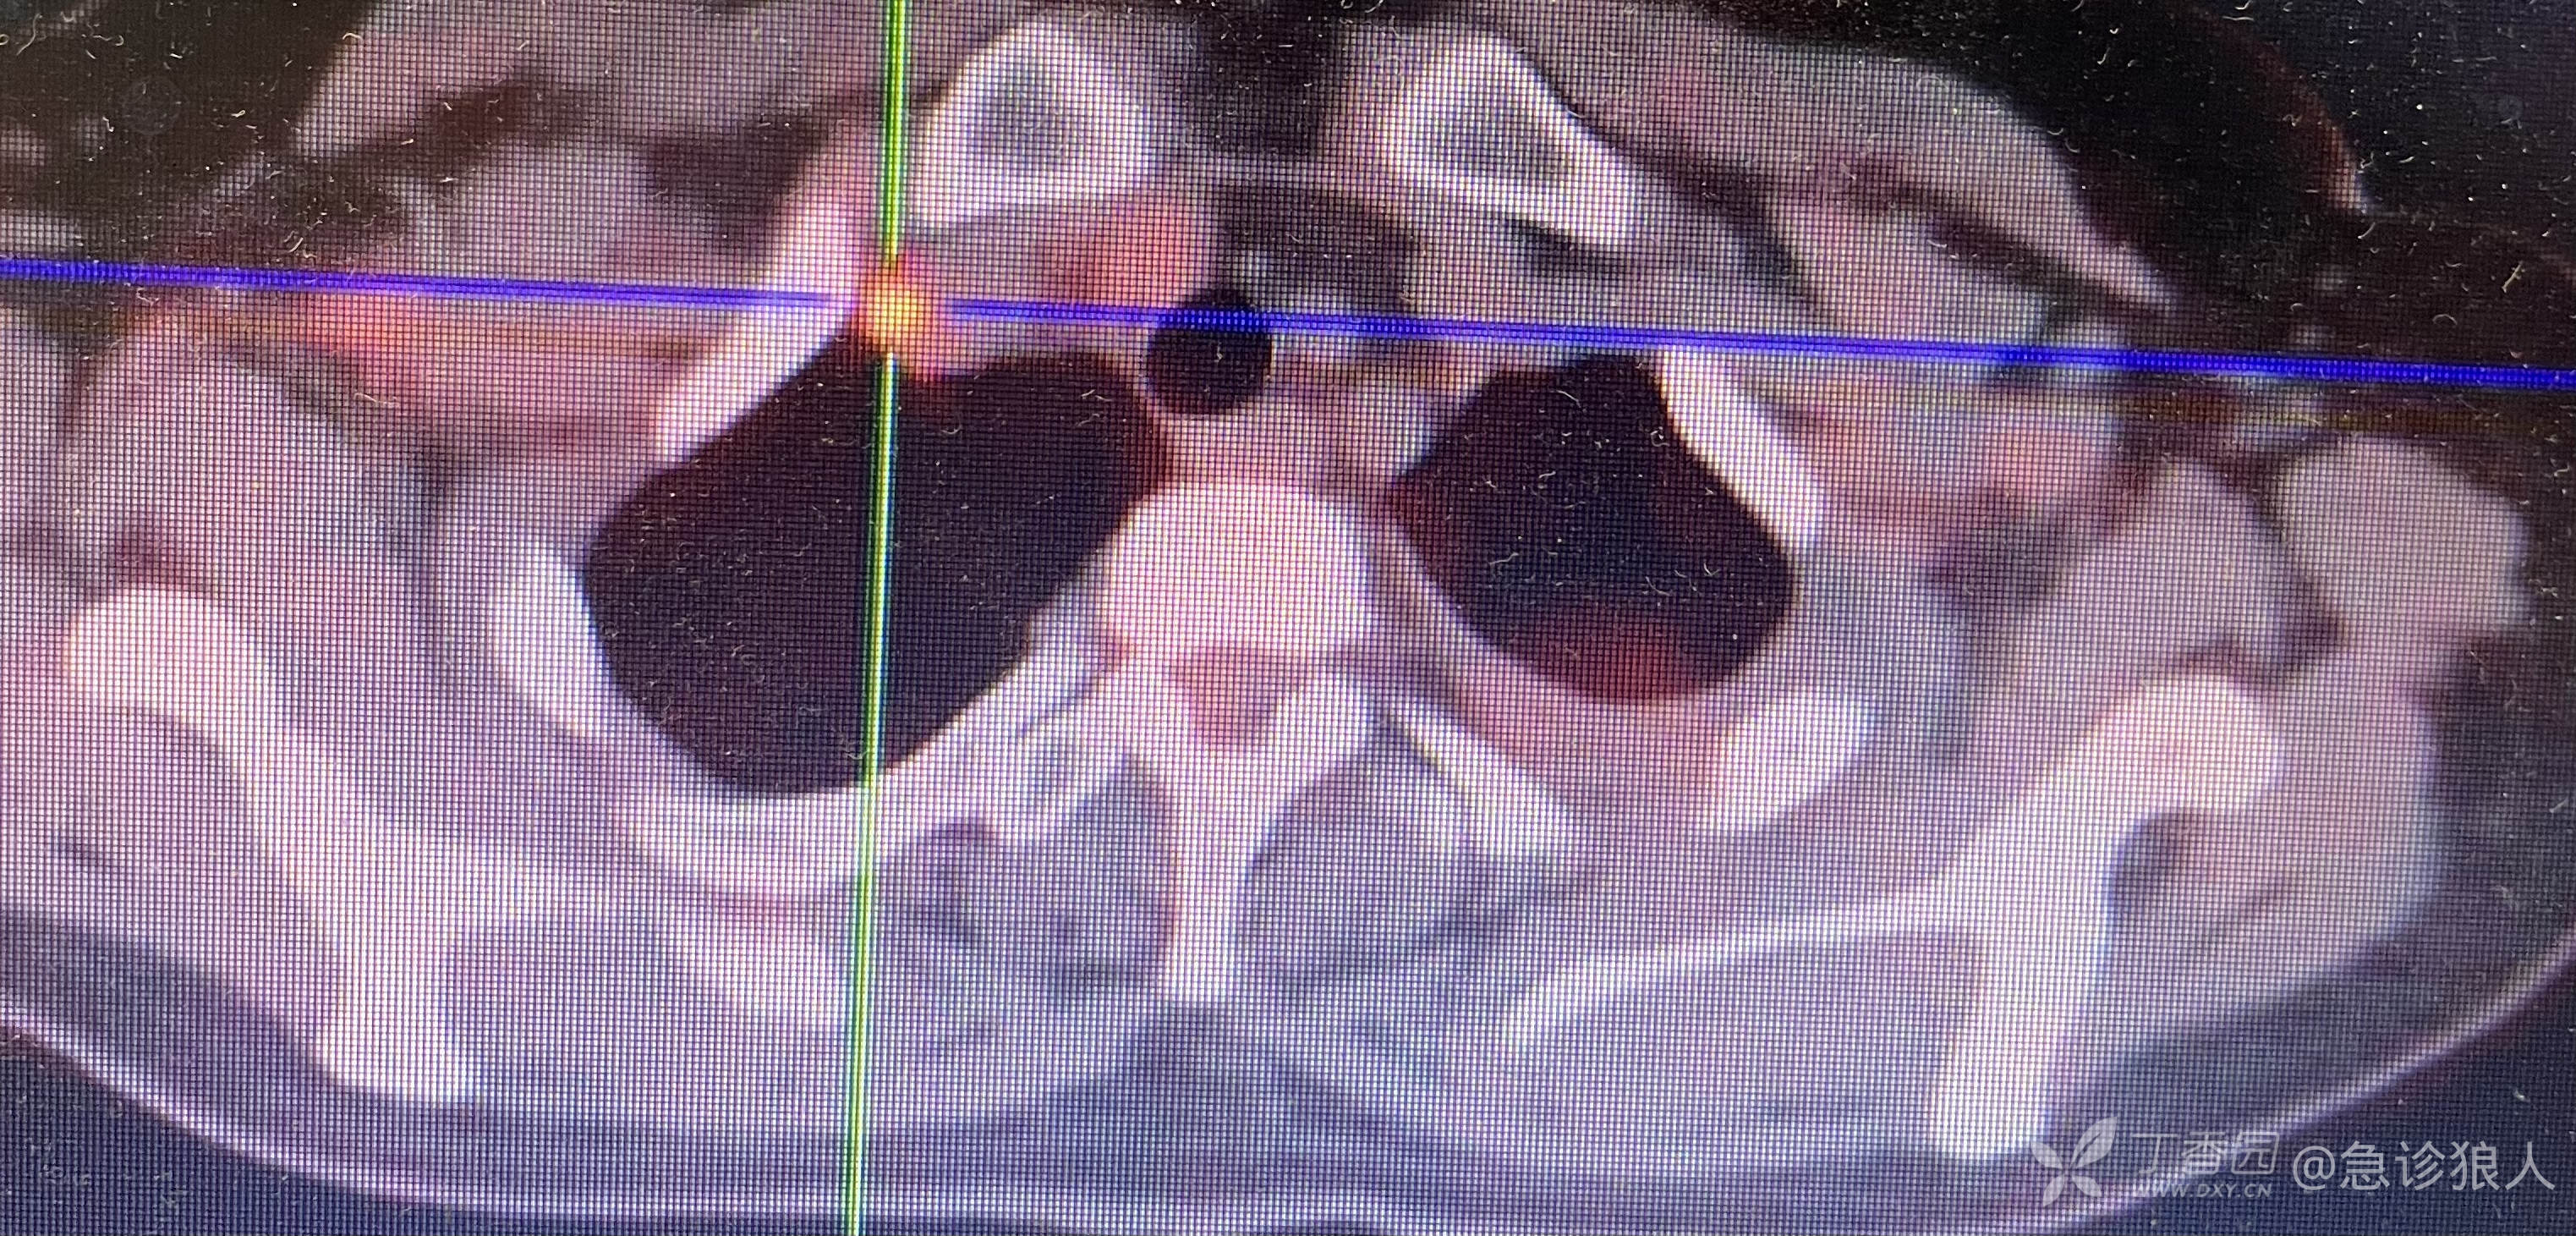

当班医生也怀疑肺栓塞,所以完善了肺动脉CTA,结果支持,如此:

诊断:双肺动脉栓塞,上腔静脉、右锁骨上动脉栓塞,左下肺叶多发斑块影,炎症可能性大,右下肺叶结节,纵隔内淋巴结肿大?